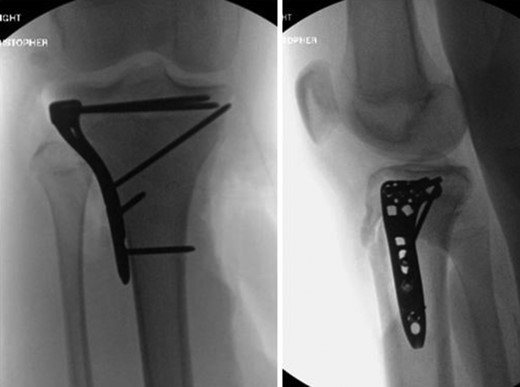

Patient is a 14-year-old male who slipped and fell while jumping off of a diving board and landed onto a flexed right knee. The patient was stable on presentation and neurovascularly intact with the knee locked in flexion. Skin was tenting anteriorly over the tibial tubercle and his compartments were swollen but compressible. A single plain film view (Fig. 1) was obtained prior to orthopaedic consultation. Closed reduction under sedation and splitting was attempted in the ED with partial but unsatisfactory improvement. Post-reduction radiographs (Fig. 2) demonstrated a tibial tubercle fracture with extension through the entire proximal tibial physis with metaphyseal involvement posteromedially. We classified this as a type IV tibial tubercle fracture, Salter–Harris II variant. In conjunction with patient and family we planned for urgent closed versus open reduction and application of knee-spanning external fixator. Immediately prior to surgery in the pre-operative holding area, the patient noted increasing right leg pain. In the operating room (OR), a marked increase in swelling with tense skin was observed. Due to rapidly progressive swelling and nature of the fracture, the decision was made to proceed with a 4-compartment fasciotomy of the right leg. The medial-sided fasciotomy (Fig. 3) revealed significant bulging of the superficial and deep compartments; however, the anterior and lateral compartments were less swollen. The fracture was unable to be closed reduced intraoperatively, therefore proximal extension of the medial fasciotomy wound was performed to open and reduce the fracture under direct visualization. Anatomic reduction was achieved and a knee-spanning external fixator was applied (Fig. 4). Approximately 72 hours later the patient was brought back to the OR for irrigation and debridement, lateral wound closure, and medial wound vacuum placement. Another 72 hours later, he returned to the OR for removal of the external fixator, ORIF, and split-thickness skin grafting of the medial fasciotomy site. An anterolateral approach was used with a 3.5 mm proximal tibial locking plate (Fig. 5). At most recent follow-up (Fig. 6), six months post-op, the patient is pain free, ambulating without assistive device, and has returned to all desired activities.

AP and lateral radiographs after attempted closed reduction which reveal type IV tibial tubercle fracture with posteromedial metaphyseal extension (Salter–Harris II variant).

AP and lateral radiographs following open reduction and application of knee-spanning external fixator.

AP and lateral intraoperative fluoroscopic images following ORIF with proximal tibial locking plate.